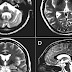

Both MRI and CT scanning frequently show a decrease in the size of the cerebellum and pons in those with cerebellar features. The putamen is hypodense on T2-weighted MRI and may show an increased deposition of iron in Parkinsonian form. In cerebellar form, a "hot cross" sign has been emphasized; it reflects atrophy of the pontocereballar fibers that manifest in T2 signal intensity in atrophic pons.